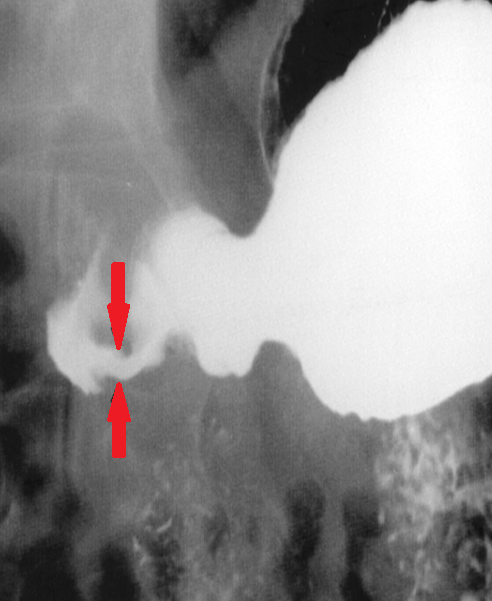

Barium swallow. Red arrow — previous Nissen fundoplication. Yellow arrow — narrowed distal esophagus with tapering of its terminal segment. Green outline — right paraesophageal hiatal hernia (Courtesy Dr. V. Penopoulos)